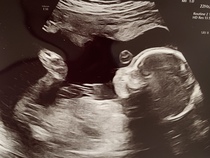

Here are a few photos of our little pickle - I'm obsessed with those little toes x

@danielasummer omg those feet I'm obsessed 👣👣👣